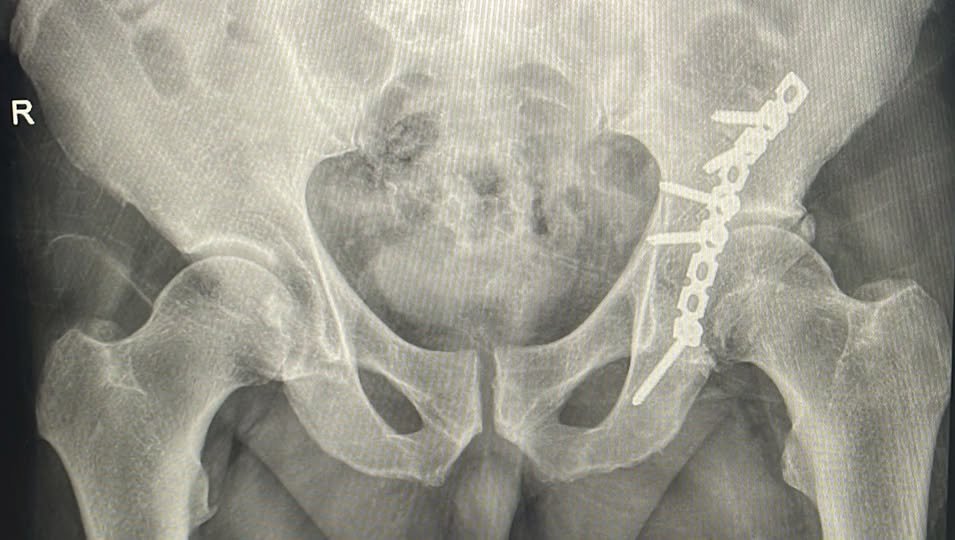

Második alkalommal végeztek eredményes műtétet a Csíkszeredai Megyei Sürgősségi Kórházban úgynevezett acetabulum törés (csípőízületi vápatörés) kezelésére. Ez egy ritka, de súlyos sérülés, amely különösen nagy odafigyelést igényel.

Az említett sérülés nagy erejű traumák, például közúti balesetek következményeként jelentkeznek, és összetett műtéti megoldást, valamint hosszú rehabilitációs folyamatot igényelnek, hogy megelőzzék a maradandó mozgáskorlátozottságot.

A műtét során az elmozdult csontdarabokat először visszahelyezik a normál helyzetükbe.

A helyes csontredukciót röntgenkészülékkel ellenőrzik. A műtétet követő gyógytorna kulcsfontosságú a felépüléshez. Általában 9-12 hónapig tart, amíg a törés teljesen meggyógyul.

A helyes csontredukciót röntgenkészülékkel ellenőrzik

Fotó: Csíkszeredai Megyei Sürgősségi Kórház/Facebook